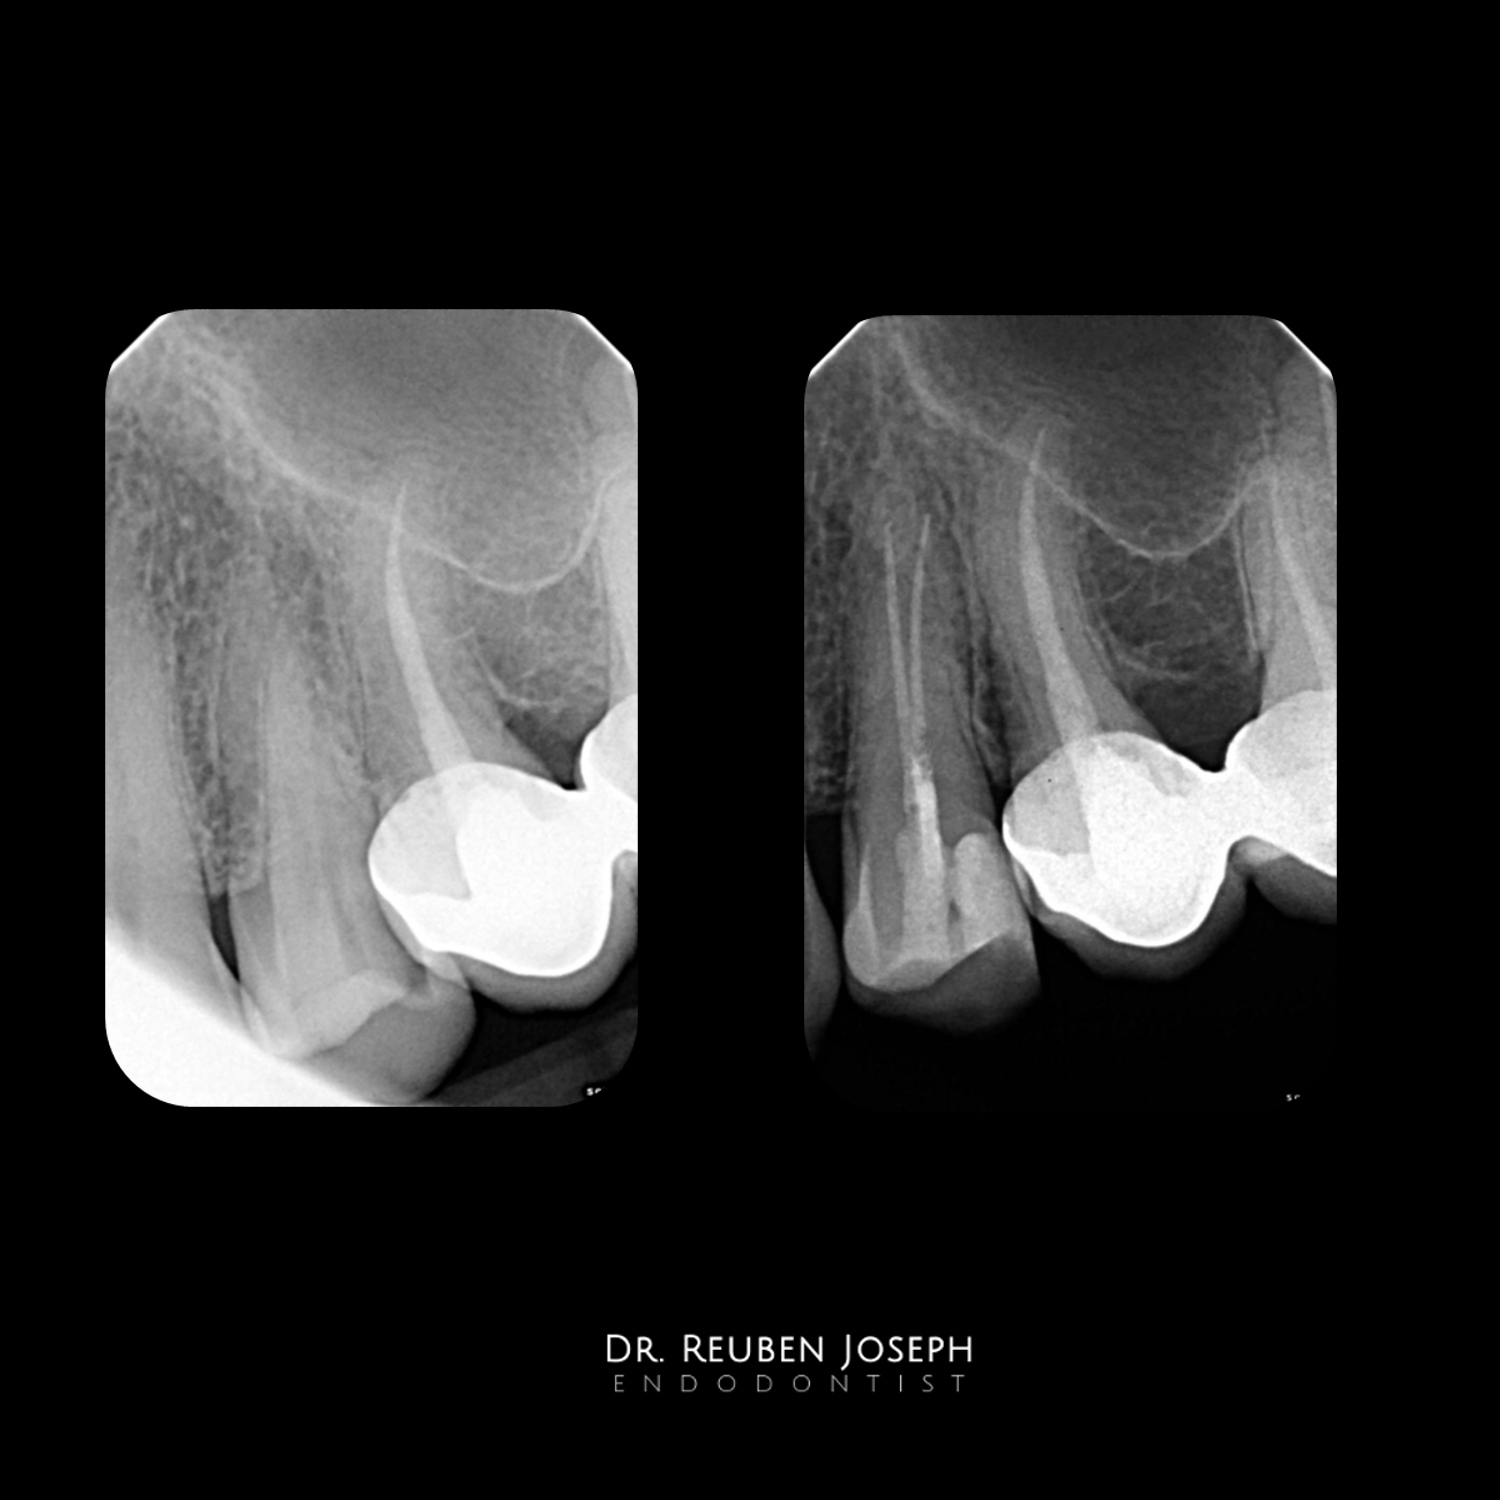

Nothing  special. A few premolars i got to treat recently with access cavity designs specific to what the clinical scenario demanded.

Case 3